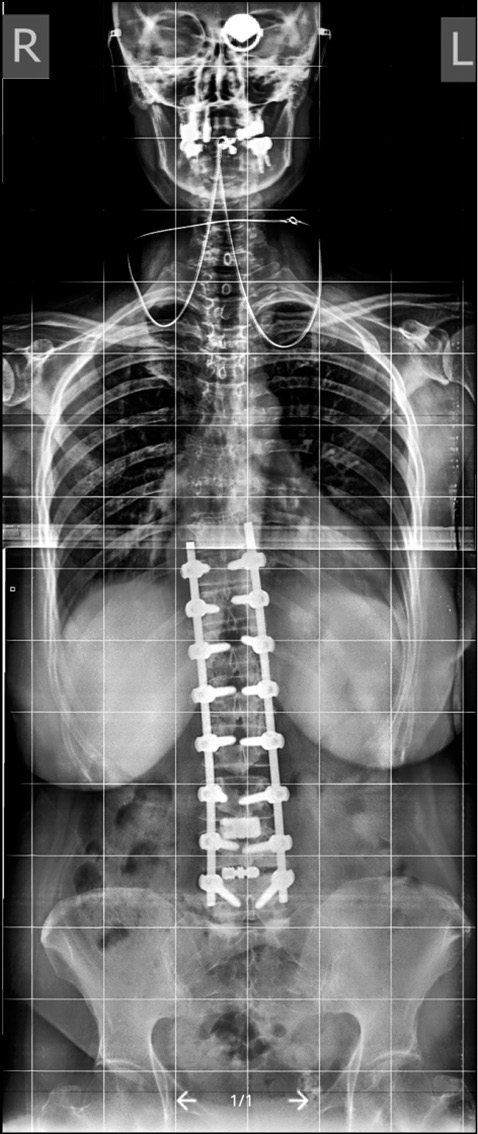

При поясничном ADS с большой степенью кривизны и подвывихе апикального ТП высокой степени всегда требуется корригирующая деформация. Как правило, в данную группу входят пациенты с углом деформации >45°, подвывихом >2 мм и отсутствием передних остеофитов в зоне операции с корректным фронтальным и сагиттальным балансом (рис. 2).

Рис. 2. Продолжительная фиксация и коррекция при ADS (фото М.Ю. Докиша). / Fig. 2. Extended fixation and correction in ADS (photo by M.Y. Dokish).

Передний спондилодез посредством трансфораминального межтелового (transforaminal lumbar interbody fusion, TLIF) или экстремально-латерального межтелового (extreme lateral interbody fusion XLIF) доступа может быть важным дополнением к стабилизации на уровне поясничного отдела позвоночника у данных лиц, особенно если планируется введение винтов в крестец и таз [28]. Снижение болевого синдрома и удачно выполненный спондилодез для коррекции ADS и восстановления LL и сагиттального баланса является ключевым в хирургическом лечении. Обычно при помощи задней инструментальной фиксации можно добиться коррекции деформации ADS, однако проблематично восстановить LL [60, 61], для чего требуется проведение переднего релиза межпозвонковых структур с поддержкой передней опорной колонны. Восстановление сагиттального баланса достигается за счет опорной способности передней колонны или выполнения остеотомий позвонков.

В 2020 г. А.А. Денисов и соавт. [62] подтвердили, что применение лордозирующих кейджей с углами 20–30° значительно увеличивает сегментарный лордоз и LL. Степень полученной коррекции сегментарного лордоза и LL была идентична прогнозируемым результатам (рис. 4, 5).

Рис. 5. Спондилограмма пациента с ADS. Выполнены протяженная транспедикулярная фиксация и передний спондилодез индивидуальными имплантами (из [62]). / Fig. 5. Spondylography of the same ADS patient. Extended transpedicular fixation and anterior spinal fusion are performed with the use of individual implants.